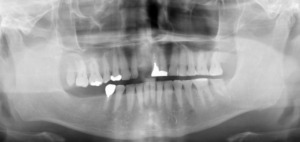

では、初診時の口腔内写真とレントゲン写真です。

初診時